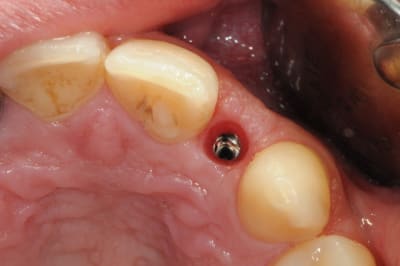

je reviens sur ce cas que j'ai un peu délaissé...

-cicatrisation

-mise en place vis de cica petit diamètre

-ensuite on augmente le diamètre en conservant et en gonflant les tissus gingivaux